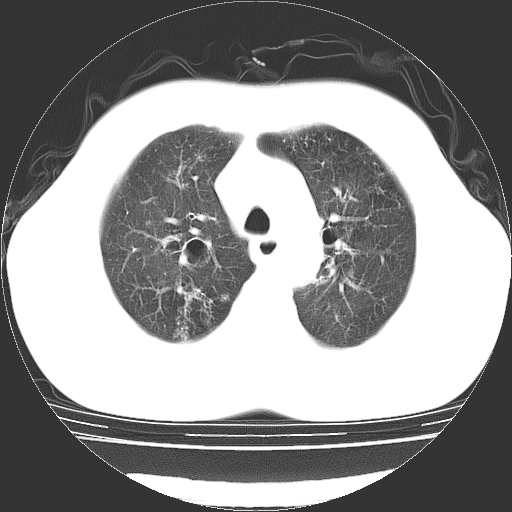

以下是引用liaoqiang在2006-12-4 16:12:00的发言:[br]局部肺叶内可见扩张的支气管壁,考虑为支扩。部份囊样影内有小液平和肺内散布斑片征影、小结节及纤维灶,提示支扩伴感染,且由于局部呈现有树芽征感染以结核可能性大。

以下是引用zhoucan076在2006-12-4 16:48:00的发言:[br]囊状支扩合并感染

以下是引用zyx168在2006-12-4 15:30:00的发言:[br]经典!支气管肺囊肿并感染。

以下是引用dyqct在2006-12-4 17:11:00的发言:[br]典型的囊状支扩合并感染。